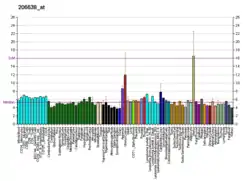

First discovered in the stomach of rats, 5-HT2B was challenging to characterize initially because of its structural similarity to the other 5-HT2 receptors, particularly 5-HT2C.[7] The 5-HT2 receptors (of which the 5-HT2B receptor is a subtype) mediate many of the central and peripheral physiologic functions of serotonin. Cardiovascular effects include contraction of blood vessels and shape changes in platelets; central nervous system (CNS) effects include neuronal sensitization to tactile stimuli and mediation of some of the effects of hallucinogenic substituted amphetamines. The 5-HT2B receptor is expressed in several areas of the CNS, including the dorsal hypothalamus, frontal cortex, medial amygdala, and meninges.[8] However, its most important role is in the peripheral nervous system (PNS) where it maintains the viability and efficiency of the cardiac valve leaflets.[9]

- Cardiac: The 5-HT2B receptor regulates cardiac structure and functions, as demonstrated by the abnormal cardiac development observed in 5-HT2B receptor null mice.[12] Excessive stimulation of this receptor causes pathological proliferation of cardiac valve fibroblasts,[13] with chronic overstimulation leading to valvulopathy.[14][15] These receptors are also overexpressed in human failing heart and antagonists of 5-HT2B receptors were discovered to prevent both angiotensin II or beta-adrenergic agonist-induced pathological cardiac hypertrophy in mouse.[16][17][18]

- Serotonin transporter: 5-HT2B receptors regulate serotonin release via the serotonin transporter, and are important both to normal physiological regulation of serotonin levels in blood plasma,[19] and with the abnormal acute serotonin release produced by drugs such as MDMA.[10] Surprisingly, however, 5-HT2B receptor activation appears to be protective against the development of serotonin syndrome following elevated extracellular serotonin levels,[20] despite its role in modulating serotonin release.